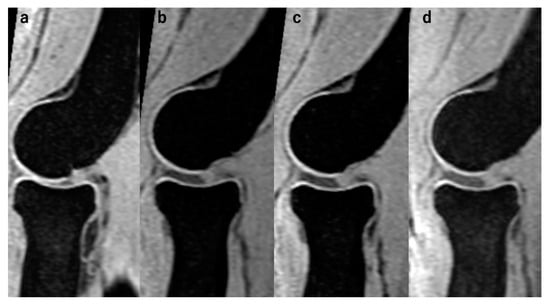

2.2. Image Acquisition

2.3. Traction MRI